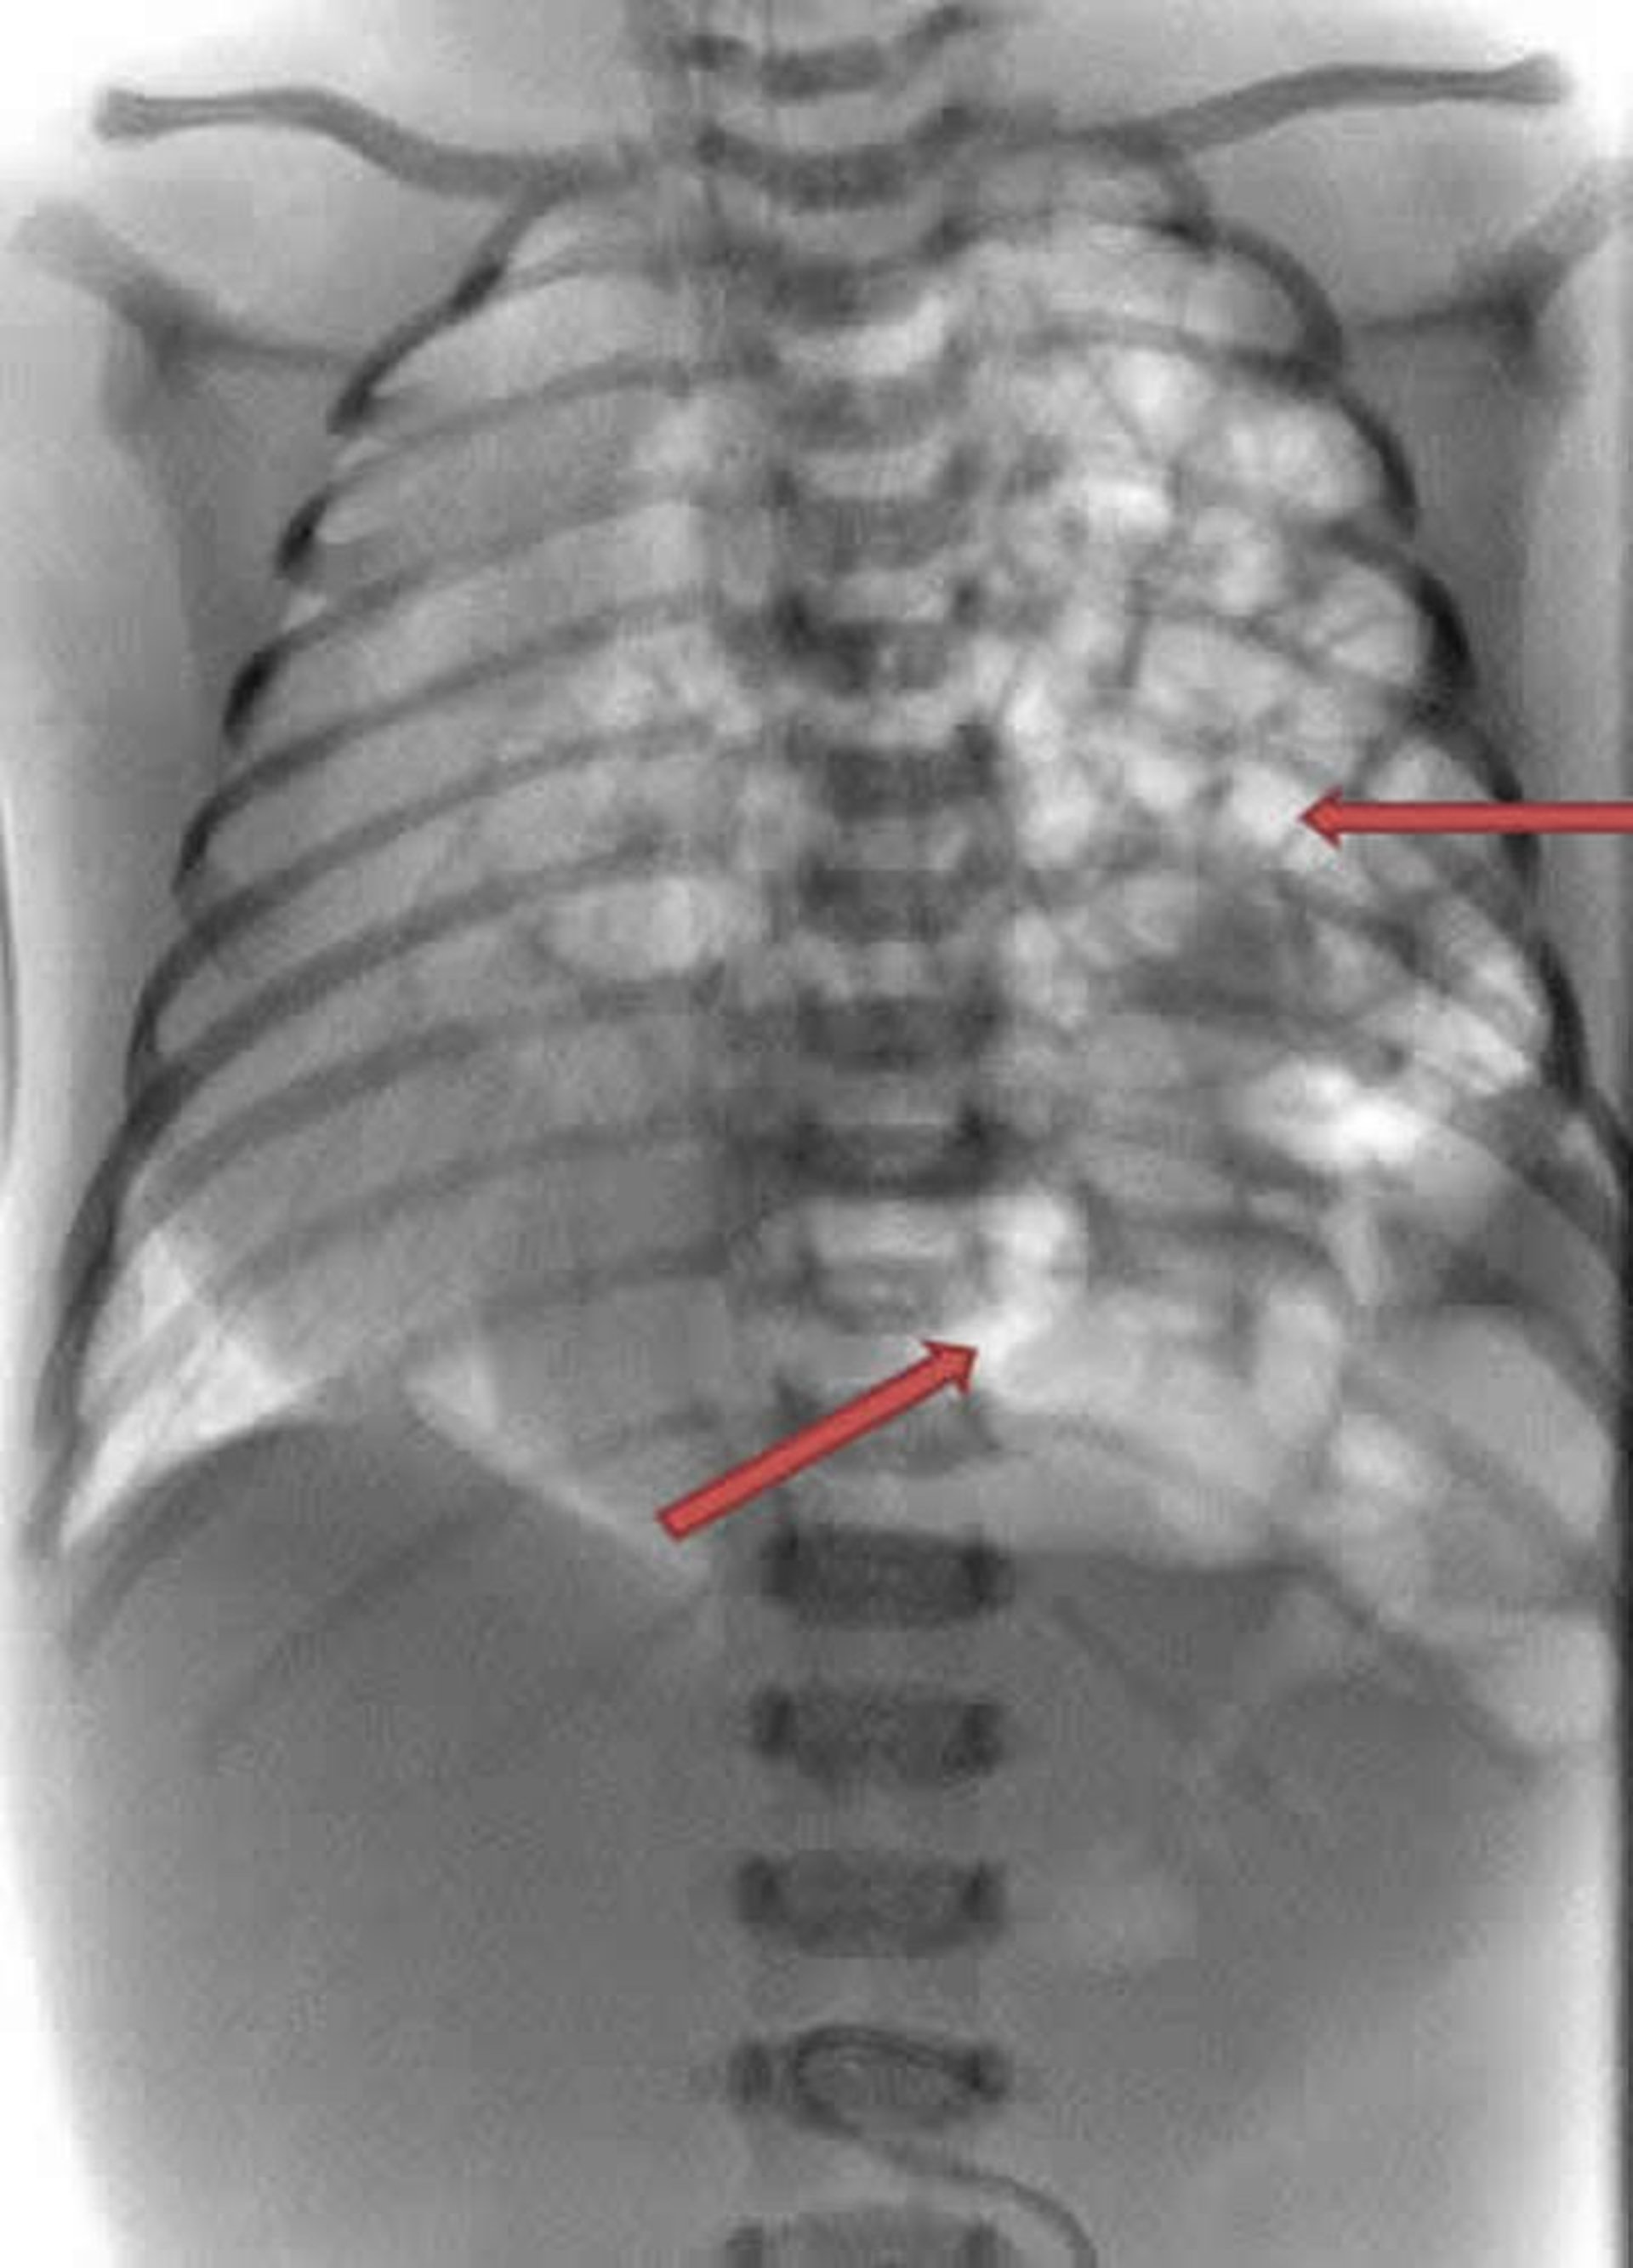

Auf dieser Röntgenaufnahme eines Neugeborenen ist zu sehen, wie der Darm (weiße Schlaufen) in die linke Seite des Brustraums hineinragen (Pfeile).